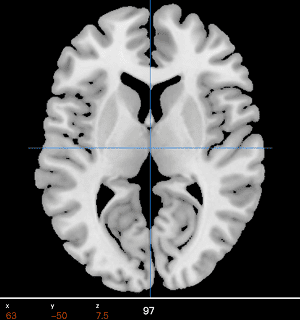

Auto preprocessing MRI Analysis BrainProbe MRI Viewer

Our technology is to employ the web diagnosis platform and deep learning model to provide the diagnosis of schizophrenia based on routine brain imaging used in the hospital.

Auto preprocessing ・ MRI Analysis・BrainProbe・MRI Viewer